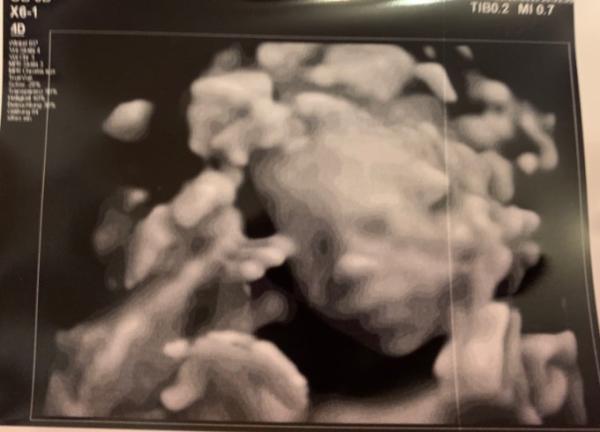

Sag mal geht es euch auch so? Wir haben in den letzten Wochen einen Termin nach dem anderen. Wir sind Mitte September aus dem Urlaub zurück, 2 Tage später Untersuchung beim Arzt, eine Woche später zur Herzfrequenzmessung ins KH. ( da war alles super) da ich viel Fruchtwasser habe den zuckertest am 10.10. ( der kleine) Werte waren bei 143, also diesen Dienstag den großen Zuckertest zum Glück mit Entwarnung. Kein Diabetes und heute beginnt der Kurs bei der Hebamme. Man man man soviel hatte ich vorher nie zu tun. Geht’s euch auch so. Bin nur froh das mit mir und dem kleinen alles super ist. Anliegend ein Bild von unserem süßen von Ende September. Wir sind so verliebt und können die Geburt Kaum erwarten

Bild zu Viel hin und her in der letzten Zeit... - Forum für Januar - Mamis